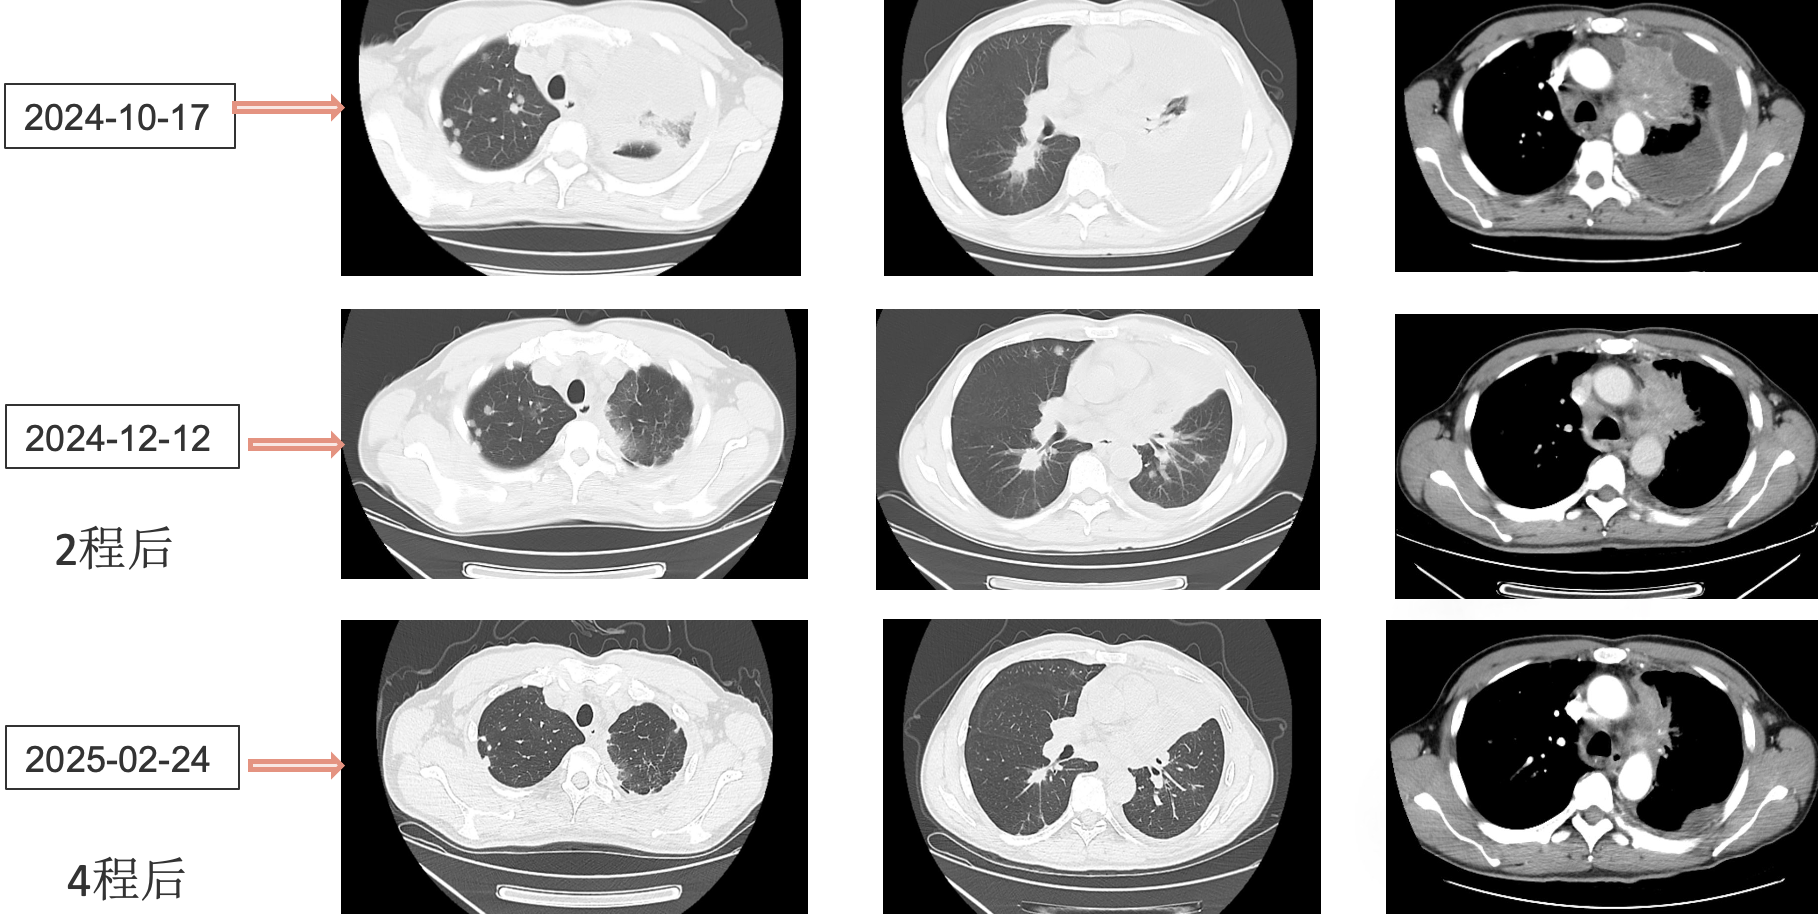

患者采用艾托组合抗体(PD-1/CTLA-4组合抗体)联合卡铂和安罗替尼治疗,同时进行血管内皮抑素胸腔灌注控制胸水。第一周期治疗后出现发热气喘等不良反应,经对症处理后症状改善。6周期治疗后影像学评估显示肺部病灶明显缩小,肝脏及淋巴结转移灶缩小,胸腔积液减少,疗效评价为PR(部分缓解),患者临床症状明显改善,生活质量显著提升。

1. 艾托组合抗体联合方案治疗6周期后,患者肺部病灶明显缩小,肝脏及淋巴结转移灶缩小,胸腔积液减少,疗效评价为PR(部分缓解);

治疗结果证实我们的选择是正确的。患者接受艾托组合抗体联合卡铂和安罗替尼治疗后,肿瘤病灶明显缩小,肝脏及淋巴结转移灶缩小,胸腔积液减少,临床获益显著,疗效评价为PR。

姚菲教授:在本例患者的治疗过程中,艾托组合抗体联合化疗和抗血管生成药物治疗对免疫治疗耐药及多线治疗后进展的NSCLC患者显示出良好疗效。患者迅速获得临床缓解,影像学评估显示病灶明显缩小,体现了艾托组合抗体克服PD-1抑制剂耐药的特性,该例患者免疫再治疗挑战成功。

总之,本例患者的治疗过程充分体现了个体化治疗的重要性。在一线免疫及其他多线治疗失败后,艾托组合抗体联合化疗和抗血管生成治疗为患者带来了显著获益。这一成功案例为驱动基因阴性、PD-L1低表达NSCLC患者的免疫再挑战治疗提供了宝贵的临床经验。